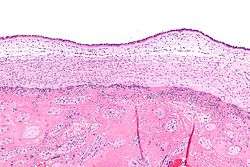

Micrograph showing chorioamnionitis. The clusters of blue dots are inflammatory cells (neutrophils, eosinophils and lymphocytes). H&E stain. | |

Chorioamnionitis can be diagnosed from a histologic examination of the fetal membranes.

Infiltration of the chorionic plate by neutrophils is diagnostic of (mild) chorioamnionitis. More severe chorioamnionitis involves subamniotic tissue and may have fetal membrane necrosis and/or abscess formation.